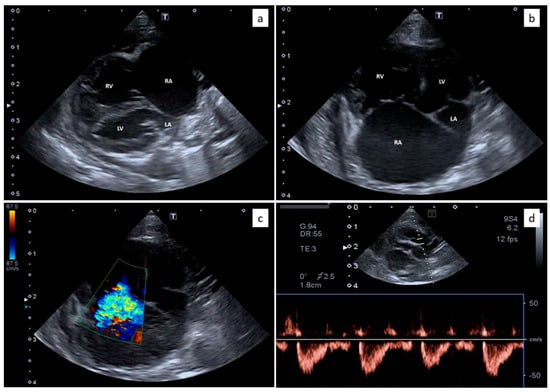

Echocardiography showed severe right atrial and ventricular dilation (Figure 2a,b) associated with right ventricular hypokinesia. Flattening of the interventricular septum was present and the internal dimension of the left ventricle was reduced. Moderate to severe tricuspid regurgitation was evident (Figure 2c) with normal morphology of the valvular leaflets. The peak velocity of the tricuspid regurgitation was 2.9 m/s. The pulmonary artery was dilated, with a pulmonary trunk to aorta ratio of 1.42. The pulmonary artery systolic flow had a proto-systolic peak (Figure 2d). Mild pericardial and pleural effusion and moderate abdominal effusion were evident. The analysis of the abdominal effusion indicated a modified transudate. All these findings were consistent with severe pre-capillary PH and R-CHF. The presence of congenital heart diseases was verified and excluded by two-dimensional and Doppler echocardiography.

Figure 2.

Echocardiography from the domestic kitten showing severe right atrial (RA) and right ventricular (RV) dilation, with reduced dimensions of the left atrium (LA) and the left ventricle (LV) (a,b). Moderate to severe tricuspid regurgitation was evident (c) with normal morphology of the valvular leaflets. The pulmonary artery systolic flow had a proto-systolic peak (d).